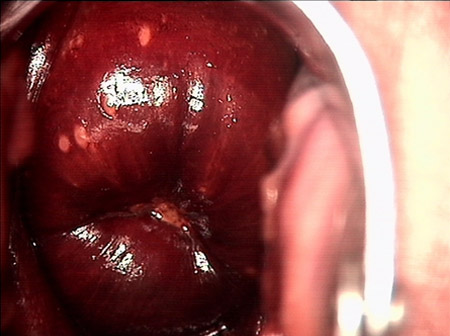

• CIN 2-3CIN 2-3

• CIN 2-3 碘著色后CIN 2-3 碘著色后

• CIN 2-3 leep術后CIN 2-3 leep術后

• CIN 2-3 修復后CIN 2-3 修復后

• CIN 2-3 修復后(圖2)CIN 2-3 修復后(圖2)